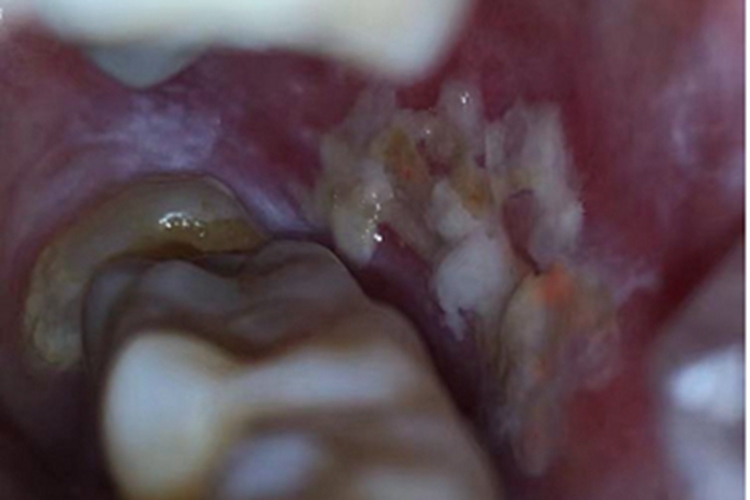

口腔白斑病患者口腔的损害形态多样,包括斑块状、溃疡状等,颜色分布不均,边界清楚,形状不规则,表面凹凸不平,患处质地柔软,患者一般无自觉症状,或自觉粗糙、木涩等。